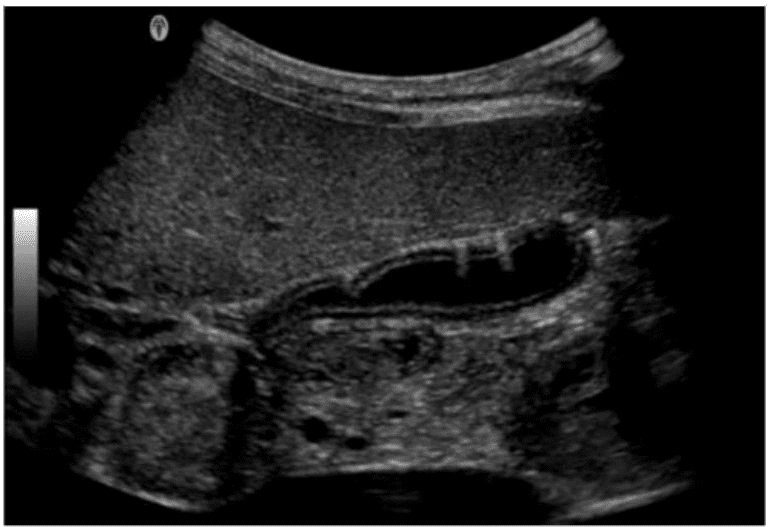

Which condition is most consistent with the findings in the image below?

Which condition is most likely depicted in this image?